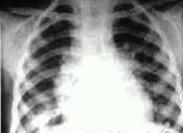

小兒急性血行播散型肺結核